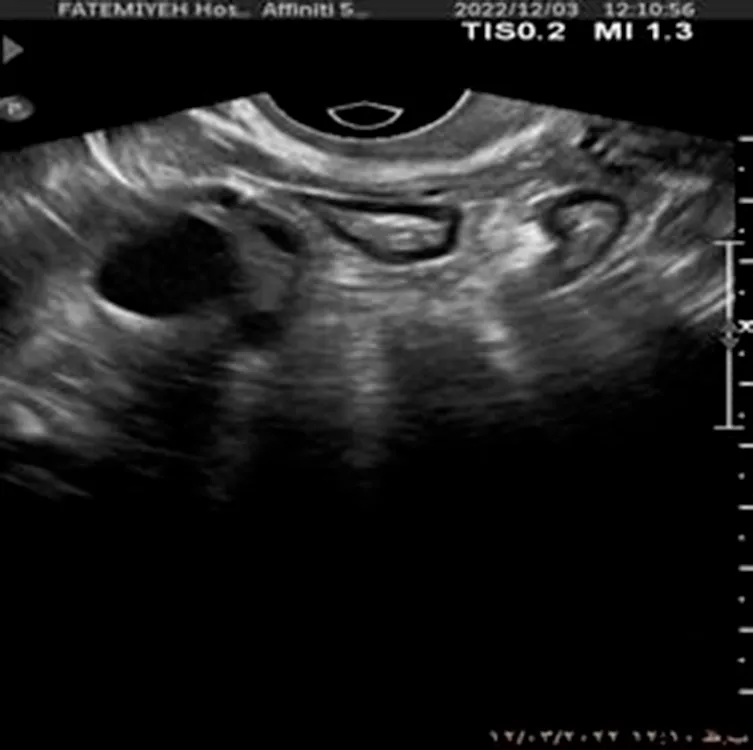

Additionally, Figure 1 below presents a sample of ultrasound images from each of the three classes, demonstrating the visual differences between the conditions and the challenges involved in classification.

Figure 1

www.frontiersin.org

Figure 1. Sample ultrasound images from the dataset, representing the three classes: (a) Normal, (b) Dominant Follicle, and (c) Polycystic Ovary Syndrome (PCO). These examples highlight the visual differences between the classes used for muticlass classification.